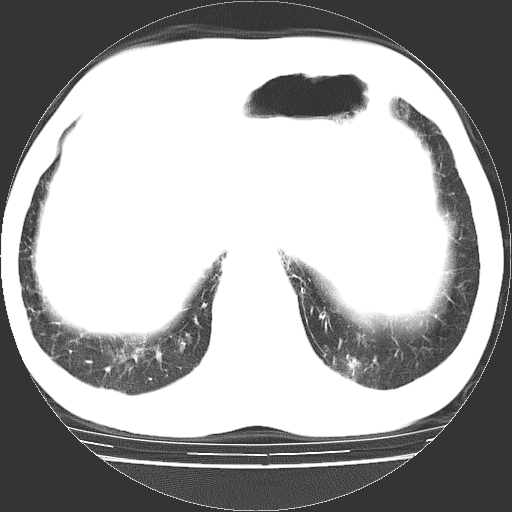

以下是引用hhcckk在2009-1-1 15:38:00的发言:[br]左下肺少许絮状模糊影--考虑感染[br]两肺散在小点状密度增高影--结合病史考虑矽肺?[br]气管壁钙化--可能由于老年退变性引起的